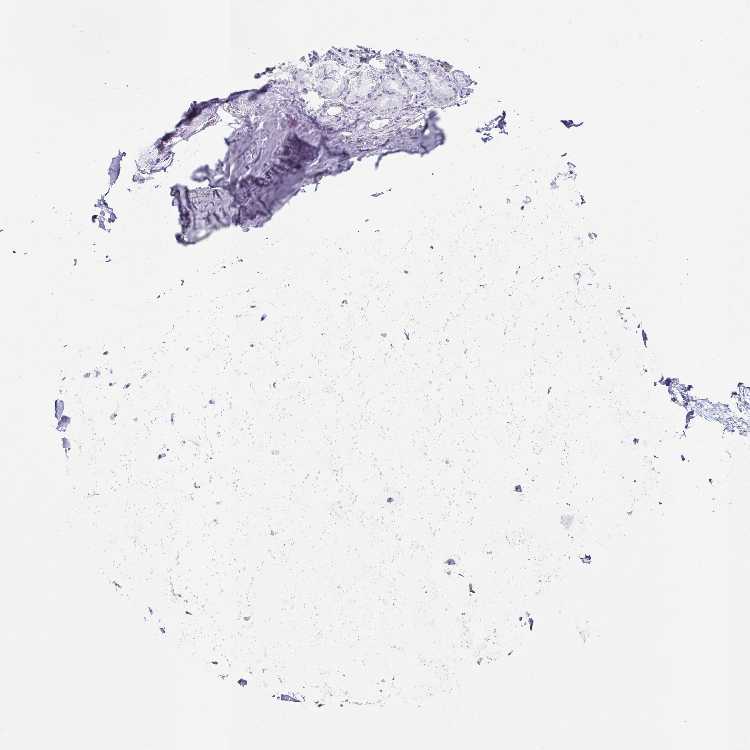

SOFT TISSUE 2 - Antibody stainingi

Antibody staining in the annotated cell types in the current human tissue is reported as not detected, low, medium, or high, based on conventional immunohistochemistry profiling in selected tissues. This score is based on the combination of the staining intensity and fraction of stained cells.

Each image is clickable and will lead to virtual microscopy that enables deeper exploration of all samples and also displays staining intensity scores, fraction scores and subcellular localization as well as patient and tissue information for each sample.

Antibody HPA046376

Fibroblasts Not detected